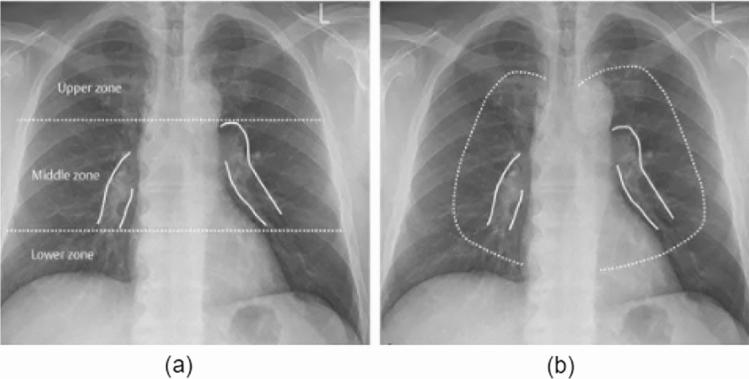

COVID-19 has been a global pandemic. Flattening the curve requires intensive testing, and the world has been facing a shortage of testing equipment and medical personnel with expertise. There is a need to automate and aid the detection process. Several diagnostic tools are currently being used for COVID-19, including X-Rays and CT-scans. This study focuses on detecting COVID-19 from X-Rays. We pursue two types of problems: binary classification (COVID-19 and No COVID-19) and multi-class classification (COVID-19, No COVID-19 and Pneumonia). We examine and evaluate several classic models, namely VGG19, ResNet50, MobileNetV2, InceptionV3, Xception, DenseNet121, and specialized models such as DarkCOVIDNet and COVID-Net and prove that ResNet50 models perform best. We also propose a simple modification to the ResNet50 model, which gives a binary classification accuracy of 99.20% and a multi-class classification accuracy of 86.13%, hence cementing the ResNet50's abilities for COVID-19 detection and ability to differentiate pneumonia and COVID-19. The proposed model's explanations were interpreted via LIME which provides contours, and Grad-CAM, which provides heat-maps over the area(s) of interest of the classifier, i.e., COVID-19 concentrated regions in the lungs, and realize that LIME explains the results better. These explanations support our model's ability to generalize. The proposed model is intended to be deployed for free use.

新冠疫情已成为一场全球大流行疾病。要实现“曲线平缓”需要进行密集检测,而全球一直面临检测设备短缺以及缺乏专业医疗人员的问题。因此有必要实现检测过程的自动化并提供辅助。目前有多种诊断工具被用于新冠病毒检测,包括X光和CT扫描。本研究聚焦于通过X光检测新冠病毒。我们探讨两类问题:二分类(新冠病毒感染和未感染)和多分类(新冠病毒感染、未感染以及肺炎)。我们研究并评估了几种经典模型,即VGG19、ResNet50、MobileNetV2、InceptionV3、Xception、DenseNet121,以及诸如DarkCOVIDNet和COVID-Net等专门模型,并证明ResNet50模型表现最佳。我们还对ResNet50模型提出了一项简单修改,其实现了二分类准确率达99.20%,多分类准确率达86.(此处有误吧,按原文应为86.13%)13%,从而巩固了ResNet50在新冠病毒检测以及区分肺炎和新冠病毒感染方面的能力。所提出模型的解释通过LIME(提供轮廓)和Grad-CAM(在分类器的感兴趣区域提供热图,即肺部新冠病毒集中区域)进行解读,并且发现LIME能更好地解释结果。这些解释支持了我们模型的泛化能力。所提出的模型旨在免费部署以供使用。